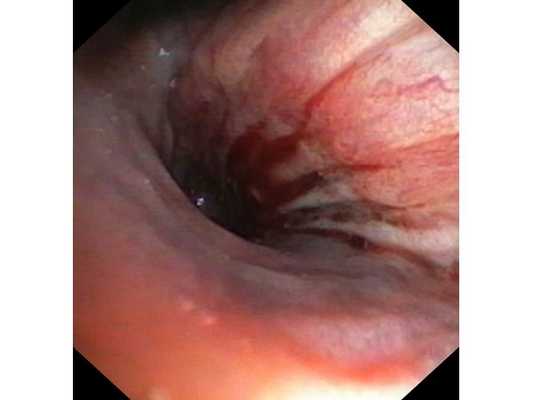

Бронхоскопическая диагностика

Среди разновидностей диагностики рака легких на ранних стадиях бронхоскопия является одной из наименее приятных, но, вместе с тем, и информативных.

Обследование проходит с применением гибкого тонкого зонда, проходящего через носовую или ротовую полость в дыхательные пути. Способ позволяет детально изучить состояние трахеи, бронхи и рассказывает о нюансах образования: его точной локализации, структуре.

Первым этапом пациенту была проведена фибробронхоскопия, по данным которой выявлено, что устье нижнедолевого бронха слева сужено за счёт подслизистого и перибронхиального распространения опухоли.